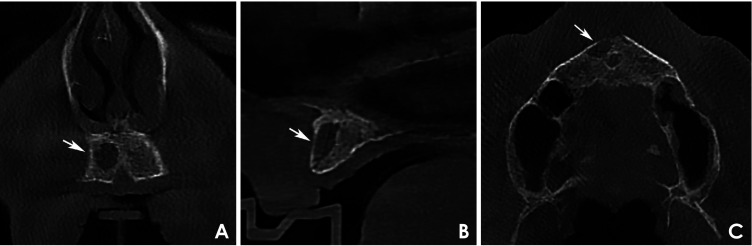

目的:本研究分析了27例多发性骨髓瘤患者在不同疾病阶段的锥形束计算机断层图像,以确定颌骨破坏模式并评估其与临床数据的关系。材料和方法:在这项横断面研究中,2名训练有素的审查员进行了标准化的、基于共识的图像分析。病变分为4种不同的骨破坏模式:弥漫性、多房性、单房性和穿孔性。临床数据从医疗记录中收集。结果:本组患者男性占51.8%,女性占48.2%,年龄以42 ~ 60岁为主。所有病例均表现为双颌弥漫性骨破坏。多房型和单房型分别占51.9%和29.6%,未发现穿孔病变。单眼模式与国际分期系统I期和Durie-Salmon期IIIA期的病例有显著相关性。结论:在研究的多发性骨髓瘤病例中,最常见的骨破坏类型是弥漫性和多房性。没有穿孔病变可能是由于使用了三维成像。在单眼模式和疾病分期之间确定了明确的关联。

Purpose: This study analyzed cone-beam computed tomography images of 27 patients with multiple myeloma at different disease stages to identify jawbone destruction patterns and assess their associations with clinical data.

Materials and methods: In this cross-sectional study, 2 trained examiners performed standardized, consensus-based image analyses. Lesions were classified into 4 distinct bone destruction patterns: diffuse, multilocular, unilocular, and punched-out. Clinical data were collected from medical records.

Results: The sample included 51.8% male and 48.2% female patients, predominantly between 42 and 60 years old. All cases exhibited diffuse bone destruction affecting both jaws. Multilocular and unilocular patterns were observed in 51.9% and 29.6% of cases, respectively, while no punched-out lesions were identified. The unilocular pattern was significantly associated with cases classified as International Staging System stage I and Durie-Salmon stage IIIA.

Conclusion: Among the studied cases of multiple myeloma, the most frequently observed bone destruction patterns were diffuse and multilocular. The absence of punched-out lesions may be attributable to the use of 3-dimensional imaging. A clear association was identified between the unilocular pattern and disease staging.